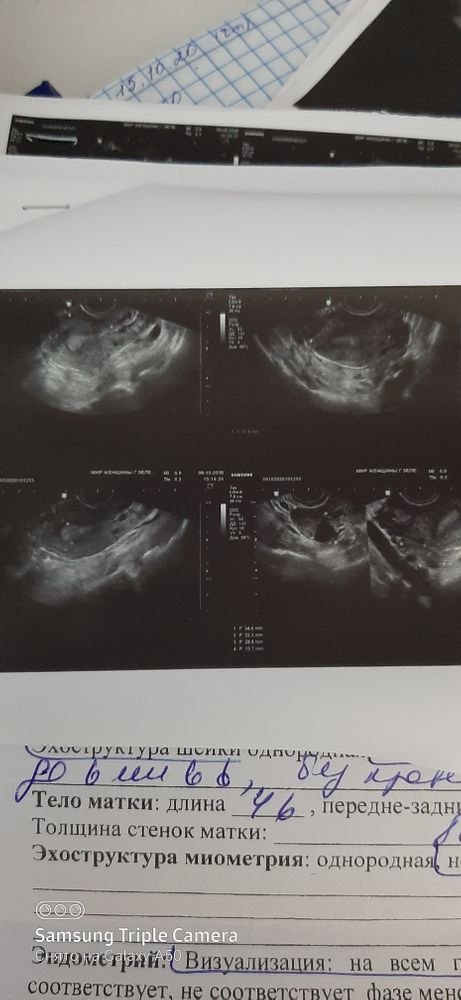

А врач вам ничего не сказал? Просто очень странные комментарии к узи и про фолликулы ничего нет. Обычно пишут количество антральных фолликулов в каждом яичнике. У вас про это "образование" и все. По диаметру оно фолликул напоминает.

Образования в шейке на полипы похожи. Я не поняла только одно 6 мм. Или много и 6 мм самое большое. Очень плохой почерк(